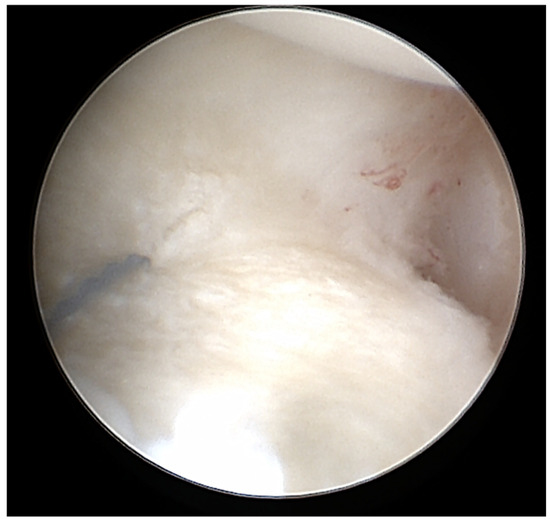

2.4. Surgery

2.5. Magnet Resonance Imaging